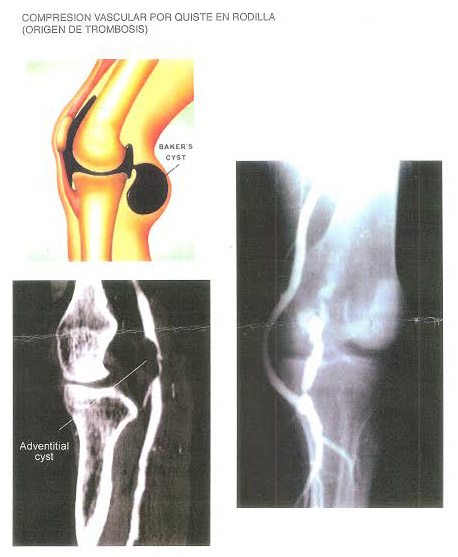

Imaginemos que hablamos de una tromboflebitis a nivel de pantorrilla. Muchos confunden con el síndrome de la pedrada o rotura fibrilar, equivocación más severa que lo anterior, pues puede conducir a fatales consecuencias. Por ejemplo, un simple esguince de tobillo puede llevar a una tromboembolia.

Tenemos muchos problemas comunes en nuestra especialidad, que producen trombosis venosa, debido a la inmovilidad a que se somete el paciente, después de haberse operado, por ejemplo, de un simple juanete.